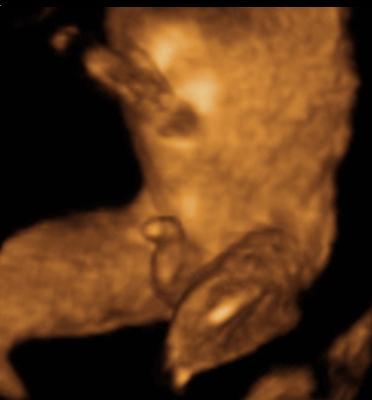

• 香港结构超声波照片

香港结构超声波照片

结构性超声波, 四维 香港, 四维结构性超声波 结构性超声波, 四维 结构性超声波, 四维 香港, 四维结构性超声波 结构性超声波, 四维 香港, 四维结构性超声波 结构性超声波, 四维 结构性超声波, 四维 结构性超声波, 四维 香港, 四维结构性超声波 结构性超声波, 四维 香港, 四维结构性超声波 结构性超声波, 四维 结构性超声波, 四维